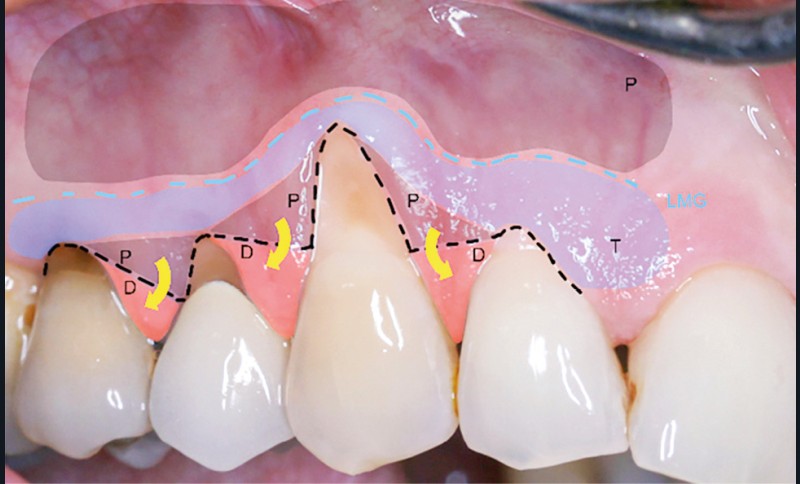

Concernant la terminologie, la classification de Cairo [6] détaille le type de récession.

La récession RT1 est une récession sans perte d’attache interproximale et où la JAC est cliniquement non détectable en zone interproximale, le recouvrement complet est possible. Lorsque la perte d’attache interproximale est inférieure ou égale à la perte d’attache vestibulaire, on parlera de récessions RT2, le recouvrement ne sera que partiel. La récession RT3 est une récession où la perte d’attache interproximale est supérieure à la perte d’attache vestibulaire, dans ce cas-là le recouvrement est impossible. Il est important aussi de savoir identifier et distinguer la récession gingivale de l’éruption passive incomplète qui est une anomalie de développement de l’éruption dentaire (fig. 1).